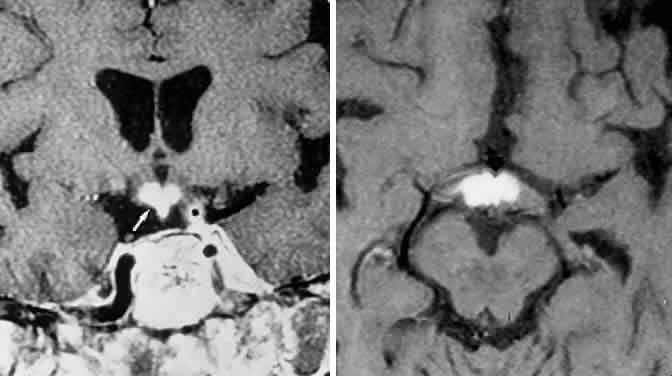

In addition to the radiologic implications mentioned previously, specific points should be emphasized. Contrast-enhanced CT and, especially, MRI have replaced all previous radiologic techniques in the detection and anatomic assessment of sellar and juxtasellar lesions. MRI has also the inherent advantage of using no radiation, nor does it require iodinated contrast injections. Although thin-section contrasted CT does indeed disclose most lesions, bone changes, and recent hemorrhage, MRI is superior in delineating distortions of optic nerves and chiasm, in displaying arteries, and in revealing fat, hemorrhage, or cyst (see Figs. 3E through M). Indeed, in a prospective study of normal volunteers, gadolinium-enhanced MRI disclosed pituitary adenomas (3 mm to 6 mm in diameter, i.e., microadenomas) in 10% of adults aged 18 to 60 years.66 T2-weighted fast spin-echo MRIs are currently the most precise sequence for demonstrating the optic nerves and chiasm, even when these structures are severely distorted by suprasellar tumor extension.67